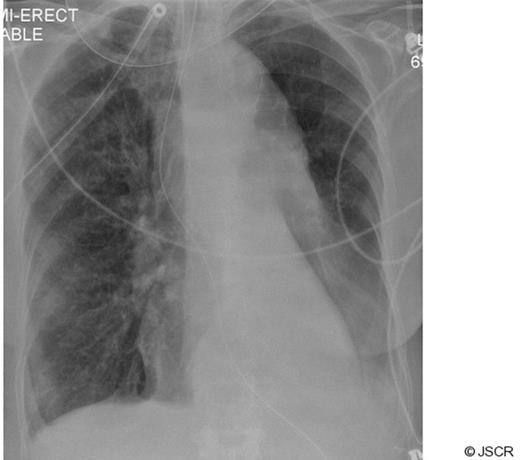

A 77 year old lady presented after an episode of chest pain and dyspnoea. Clinical examination was unremarkable apart from a low grade temperature of 37.8 oC and breath sounds were equal bilaterally. There was no evidence of cardiac ischaemia on an electrocardiogram. Inflammatory markers (white cell count and C-reactive protein) were raised. The cardiac enzyme levels were within normal limits. Empirical antibiotic therapy was instituted for a clinical diagnosis of lower respiratory tract infection. After admission the patient's condition deteriorated with increasing dyspnoea and a worsening PaO2 / FiO2 ratio. Her chest radiograph showed a complete “white-out” of her left lung field (Fig 1). Her trachea was intubated and her lungs mechanically ventilated.

Arterial oxygenation improved quickly afterwards, allowing the inspired fraction of oxygen to be reduced to 0.3, and there were no complications from the procedure. A subsequent radiograph confirmed re-inflation of the left lung field (Fig 4).